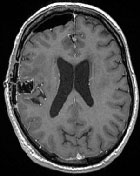

Cas clinique n°2. Patiente de 41 ans, droitière, KPS 100 présentant des céphalées inaugurales qui conduisent à la découverte d’une lésion nécrotique temporale droite. Résection sub-totale de la prise de contraste sous neuronavigation IRM...